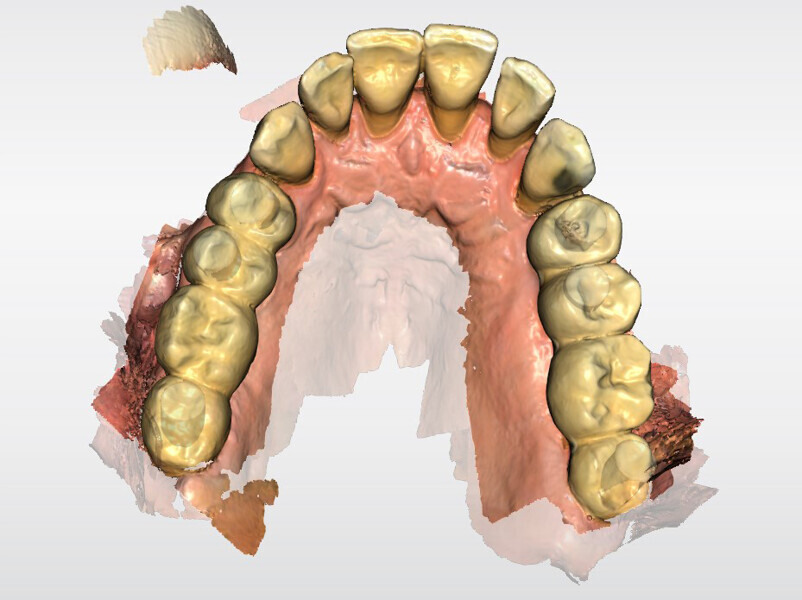

After a healing period of six months (Fig. 6), an intra-oral scan was performed at abutment level together with a scan of the existing temporary bridges in relation to the opposing arch (Figs. 7–11).

All files were imported into Atlantis Scan Upload for ordering of the Atlantis BridgeBase frameworks (Dentsply Sirona; Fig. 12). After approval of the Atlantis BridgeBase and core file designs, the Atlantis BridgeBase frameworks and zirconia shells were manufactured (Figs. 13–16).